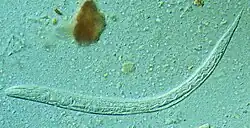

| First stage larva (L1) of S. stercoralis | |

Strongyloides (from Greek strongylos, round, + eidos, resemblance), anguillula, or threadworm is a genus of small nematode parasites, belonging to the family Strongylidae, commonly found in the small intestine of mammals (particularly ruminants), that are characterized by an unusual lifecycle that involves one or several generations of free-living adult worms.